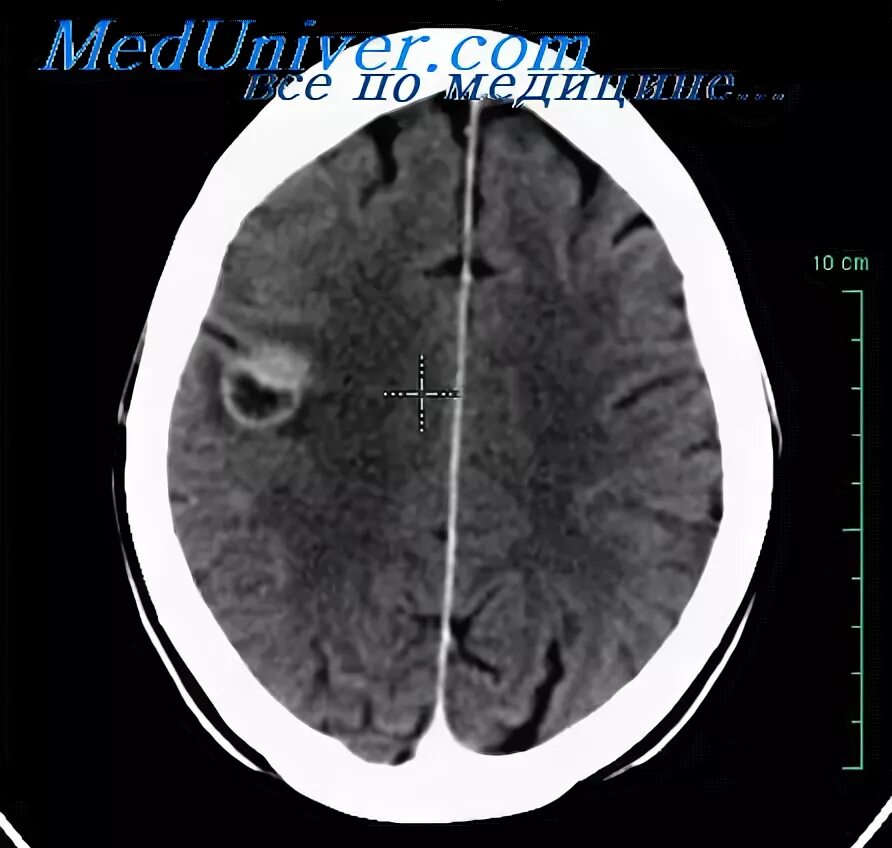

Субарахноидальное пространство лобных долей